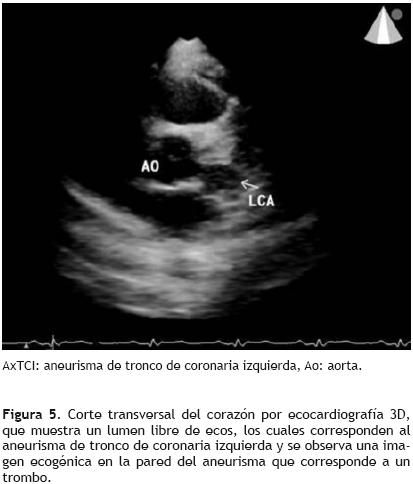

En abril del 2007, se valoró nuevamente con ecocardiograma transtorácico y transesofágico observándose el aneurisma del tronco de coronaria izquierda sin cambios con respecto a estudios previos (Figura 3). En una nueva valoración, aproximadamente un año después, se practicó una tomografía computarizada de control, en la cual no se observa crecimiento del aneurisma, así como tampoco se encuentran datos sugerentes de ruptura del mismo (Figura 4). Además, se realizó la evaluación del aneurisma de tronco con ecocardiograma tridimensional (Figura 5).